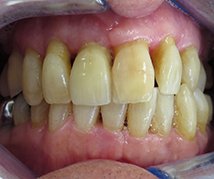

Male patient very unhappy with crooked discoloured teeth. Patient delighted with improved smile using five all ceramic crowns.

Before

After